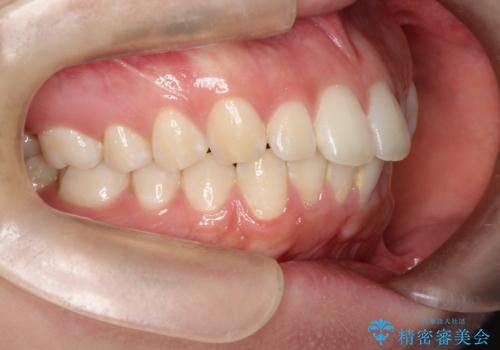

前歯の隙間を閉じたい 口元も下げたい ハーフリンガルによる抜歯矯正